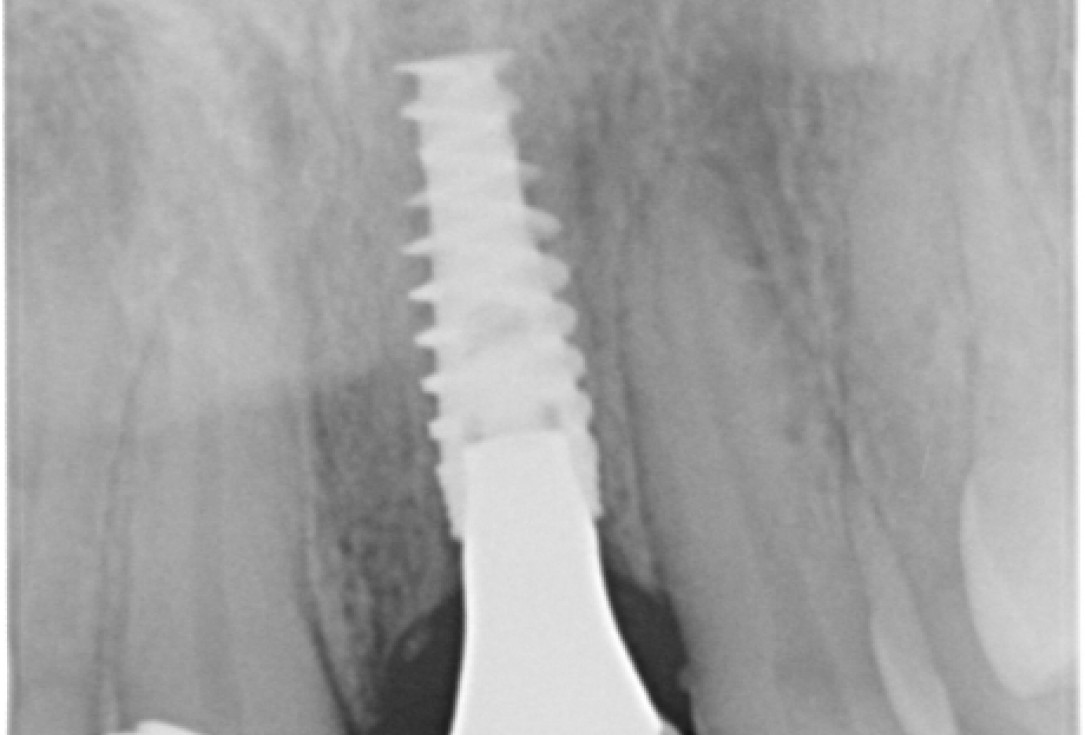

18/18 - X-ray control 15 months post-operativeGBR together with soft tissue augmentation with mucoderm® and maxresorb® - Dr. S. Scherg